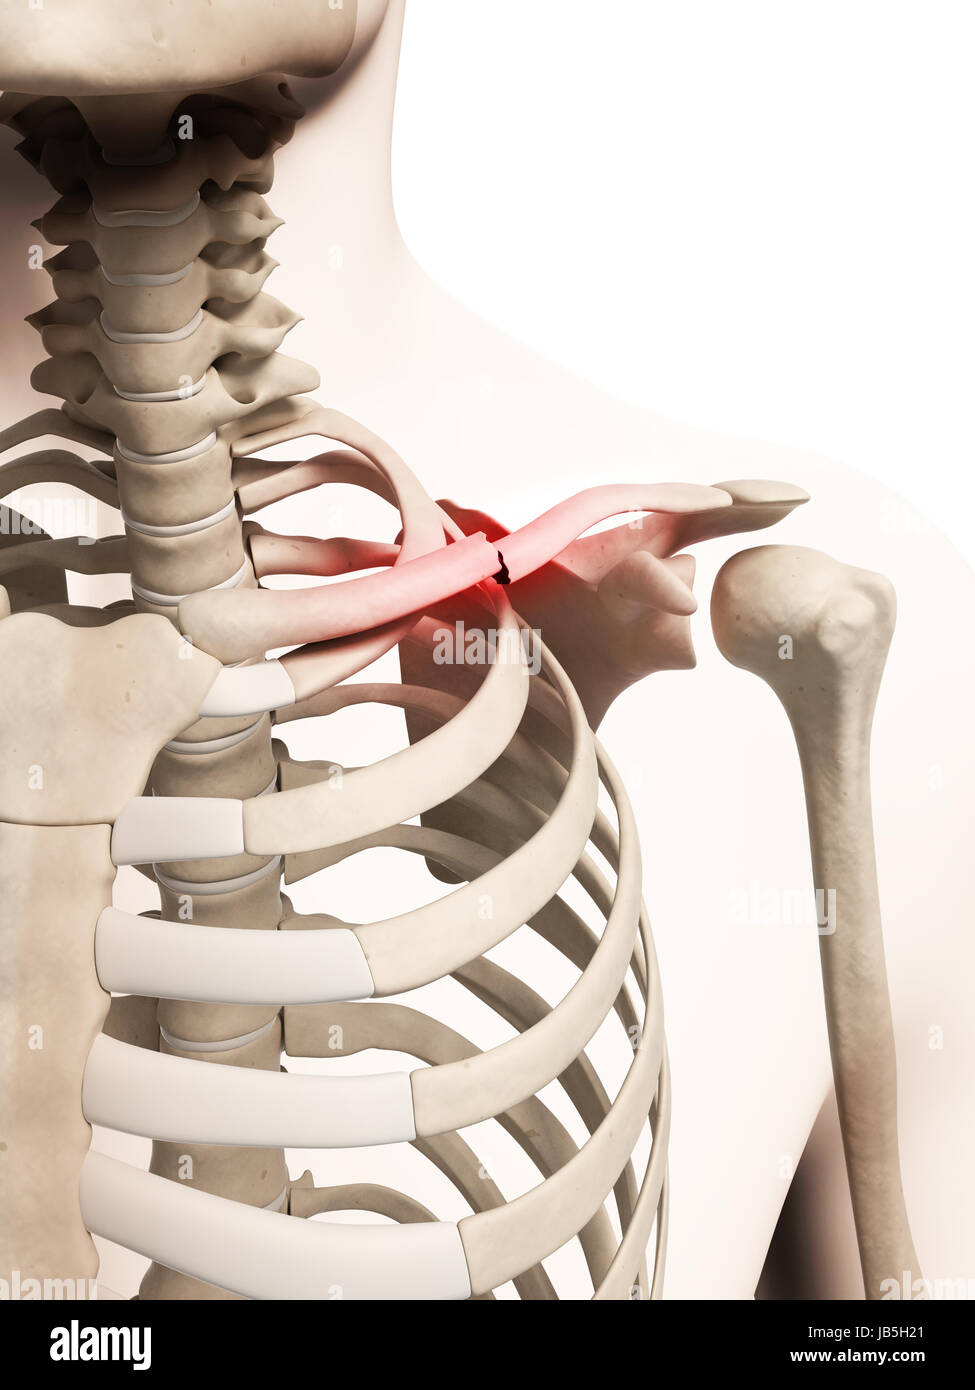

From www.alamyimages.fr

Illustration médicale d'une clavicule cassée Photo Stock Alamy Clavicule Cassee Temps Guerison 🚭 comment maximiser les chances de consolider vite et bien ? Tous ces délais sont raccourcis chez l’enfant et l’adolescent. ⏱️ temps de guérison et récupération après une fracture de la clavicule. La douleur diminue en général assez rapidement au repos, mais peut durer plusieurs semaines lors des mouvements de l’épaule. la durée varie en fonction de plusieurs. Clavicule Cassee Temps Guerison.